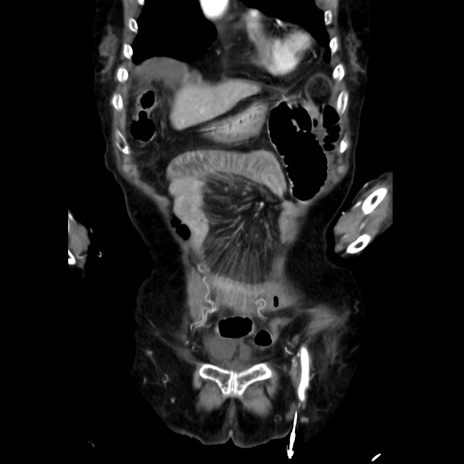

症例40(冠状断像)

【症例】90歳代女性

【主訴】腹痛・嘔吐

【現病歴】 食欲低下、嘔吐があり昨日他院受診。肺炎と診断され入院となる。入院後より腹部全体に圧痛あり。胃管留置され経過みていたが、症状持続するため、

当院転院となる。

【既往歴】胸椎圧迫骨折、胆石症

【身体所見】腹部:中央に激痛あり、圧痛あり、反跳痛不明

【データ】WBC 17100、CRP 18.82

冠状断像